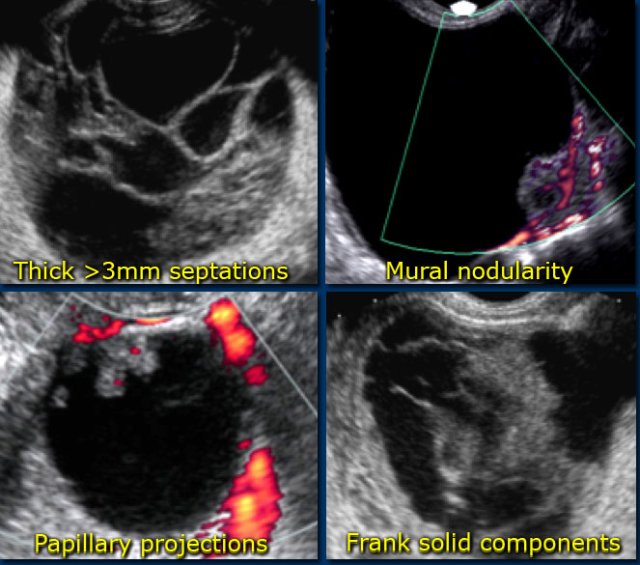

Any other cyst - possible neoplasm

All other cystic lesions are regarded as possibly neoplastic and therefore possibly malignant.

Surgical resection is needed by an oncologic gynaecologist, who may request prior imaging-based staging.

Findings indicating possible neoplasm:

- Large size

While benign lesions can be very large, the likelihood that a lesion is neoplastic increases with size.

Also the likelihood that a neoplastic lesion is malignant, increases with the size of the lesion. - Vascularized septations

The presence of septations indicates a possible neoplasm. When septations have a thickness of more than 3mm and are well-vascularized - while non-specific - both increase the likelihood that a neoplasm is malignant. - Vascularized solid components

Vascularized nodularities, papillary projections, or frank solid masses all increase the likelihood of a neoplastic nature. - Vascularized thick, irregular wall

Lesions with thin walls are more often benign and lesions with thick, irregular walls are more often malignant. However, there is some overlap, making wall thickness a less useful criterion. For example a corpus luteum cyst may also have a thickened, vascularized wall. - Secondary findings associated with malignant lesions:

Large quantities of ascites, lymphadenopathy and peritoneal deposits are strongly associated with an increased likelihood of malignancy.